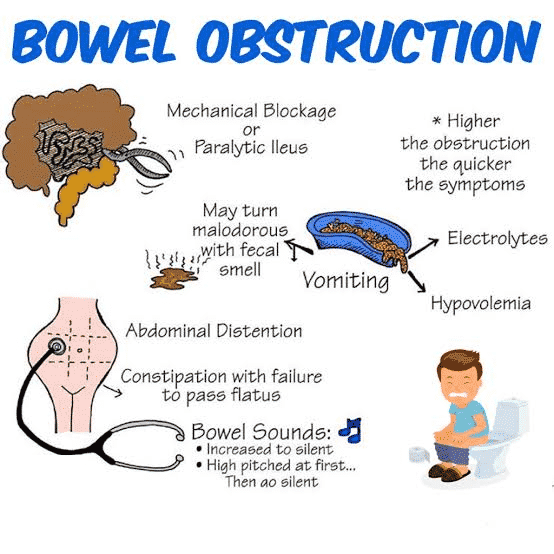

Bowel Obstruction Intestinal Obstruction MedlinePlus

Small Bowel Obstruction

Intestinal Obstruction Presentation And Treatment